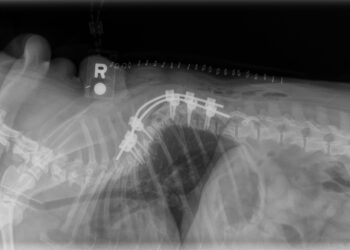

BOZEMAN, Mont., May 30, 2025 /PRNewswire/ -- Bridger Veterinary Specialists (BVS) proudly announces the inaugural BVS Neurosurgery Summit — a premier, two-and-a-half-day event focused on advancing the field of veterinary...